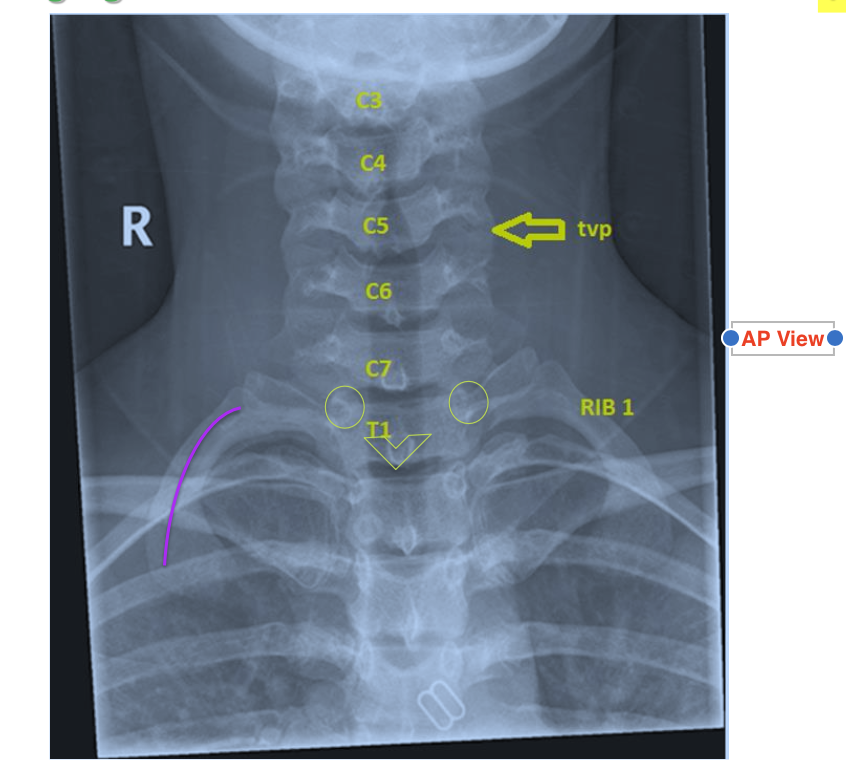

Images of Cervical Vertebrae

A

Vertebral Bodies C3 to C7

Find rib #1 and count bodies superiorly

Vertebral discs appear radiolucent between bodies

Transverse processes stick out laterally

Pedicles (eyes of the bird face)

Spinous Process (beak of bird face)%